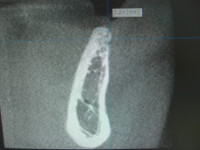

左下臼歯部のこの部位はCTコロナル画像で見てみますと骨幅が歯槽頂部で3ミリ程しかない非常に非薄で狭小な顎骨形態でしたねー。

画像で術前術後の骨幅を比較してみて頂くと解ると思いますが、しっかりした予知性のある骨幅が再製、確保できたと思います。